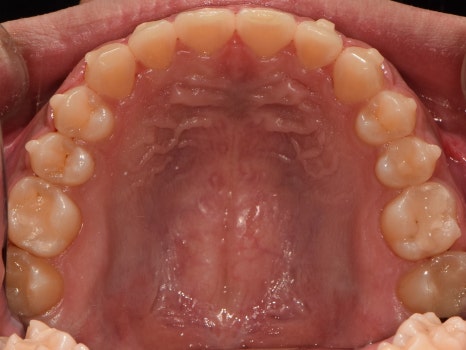

교합면에서 관찰해보면

밖으로 뻗쳐 있던 어금니들도

제 위치를 찾아 돌아온 것을 볼 수 있네요.